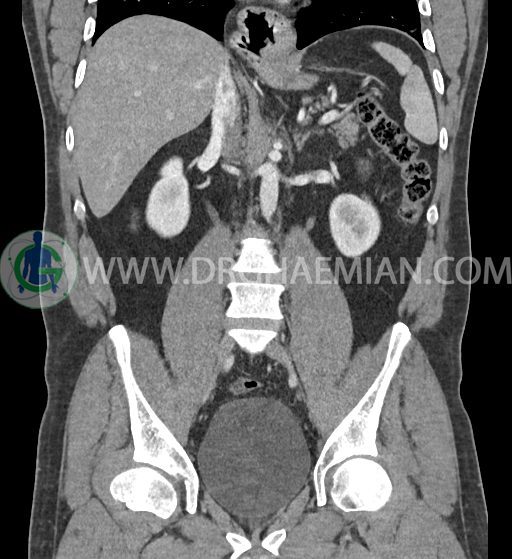

در سی تی اسکن اسپیرال شکم و لگن با کنتراست خوراکی و وریدی (مولتی دیدکتور 16 با مقاطع ظریف و بازسازی های ساژیتال و کرونال) :

ضایعه ای در کبد، کیسه صفرا، مجاری صفراوی، طحال، کلیه ها، پانکراس و آدرنالها مشهود نیست.

لنف آدنوپاتی در اطراف آئورت و IVC دیده نمیشود .

کلیه ها کنتراست را ترشح کرده اند و نمای سیستم پیلوکالیسیل و حالب دو طرف نرمال است .

ضایعه ای در معده ، روده باریک و کولون مشهود نیست .

مایع آزاد در حفره شکم و لگن رویت نمی شود.

ضایعه ای در مثانه و پروستات مشهود نیست.

-sliding hiatal hernia به ابعاد 60x44mm با جابجایی JE.junction و فوندوس معده به فضای مدیاستن خلفی دیده می شود.

-هیدرویورترونفروز جزئی دو طرفه دیده می شود که می تواند ثانویه به اتساع مثانه باشد.